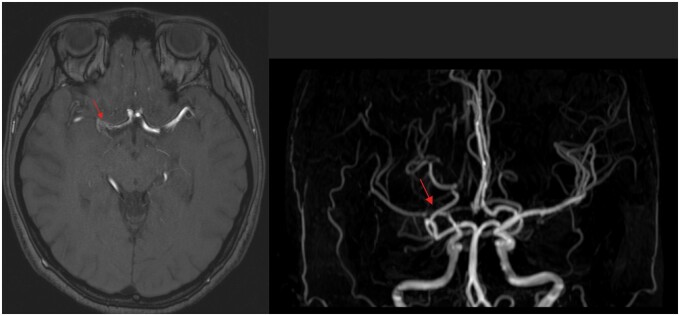

Abstract Image